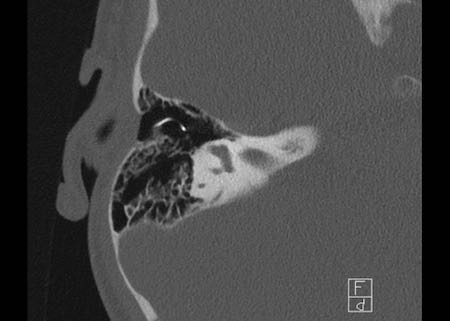

Bên trái là hình ảnh của một bé gái 2 tuổi.

Các hình ảnh từ kết quả chụp CT được thực hiện trước khi cấy ốc tai điện tử.

Quan sát thấy dị dạng nhẹ ở đỉnh ốc tai – không có sự phân tách giữa vòng thứ hai và vòng thứ ba, và trụ ốc tai xương vắng mặt.

Cống tiền đình bình thường.